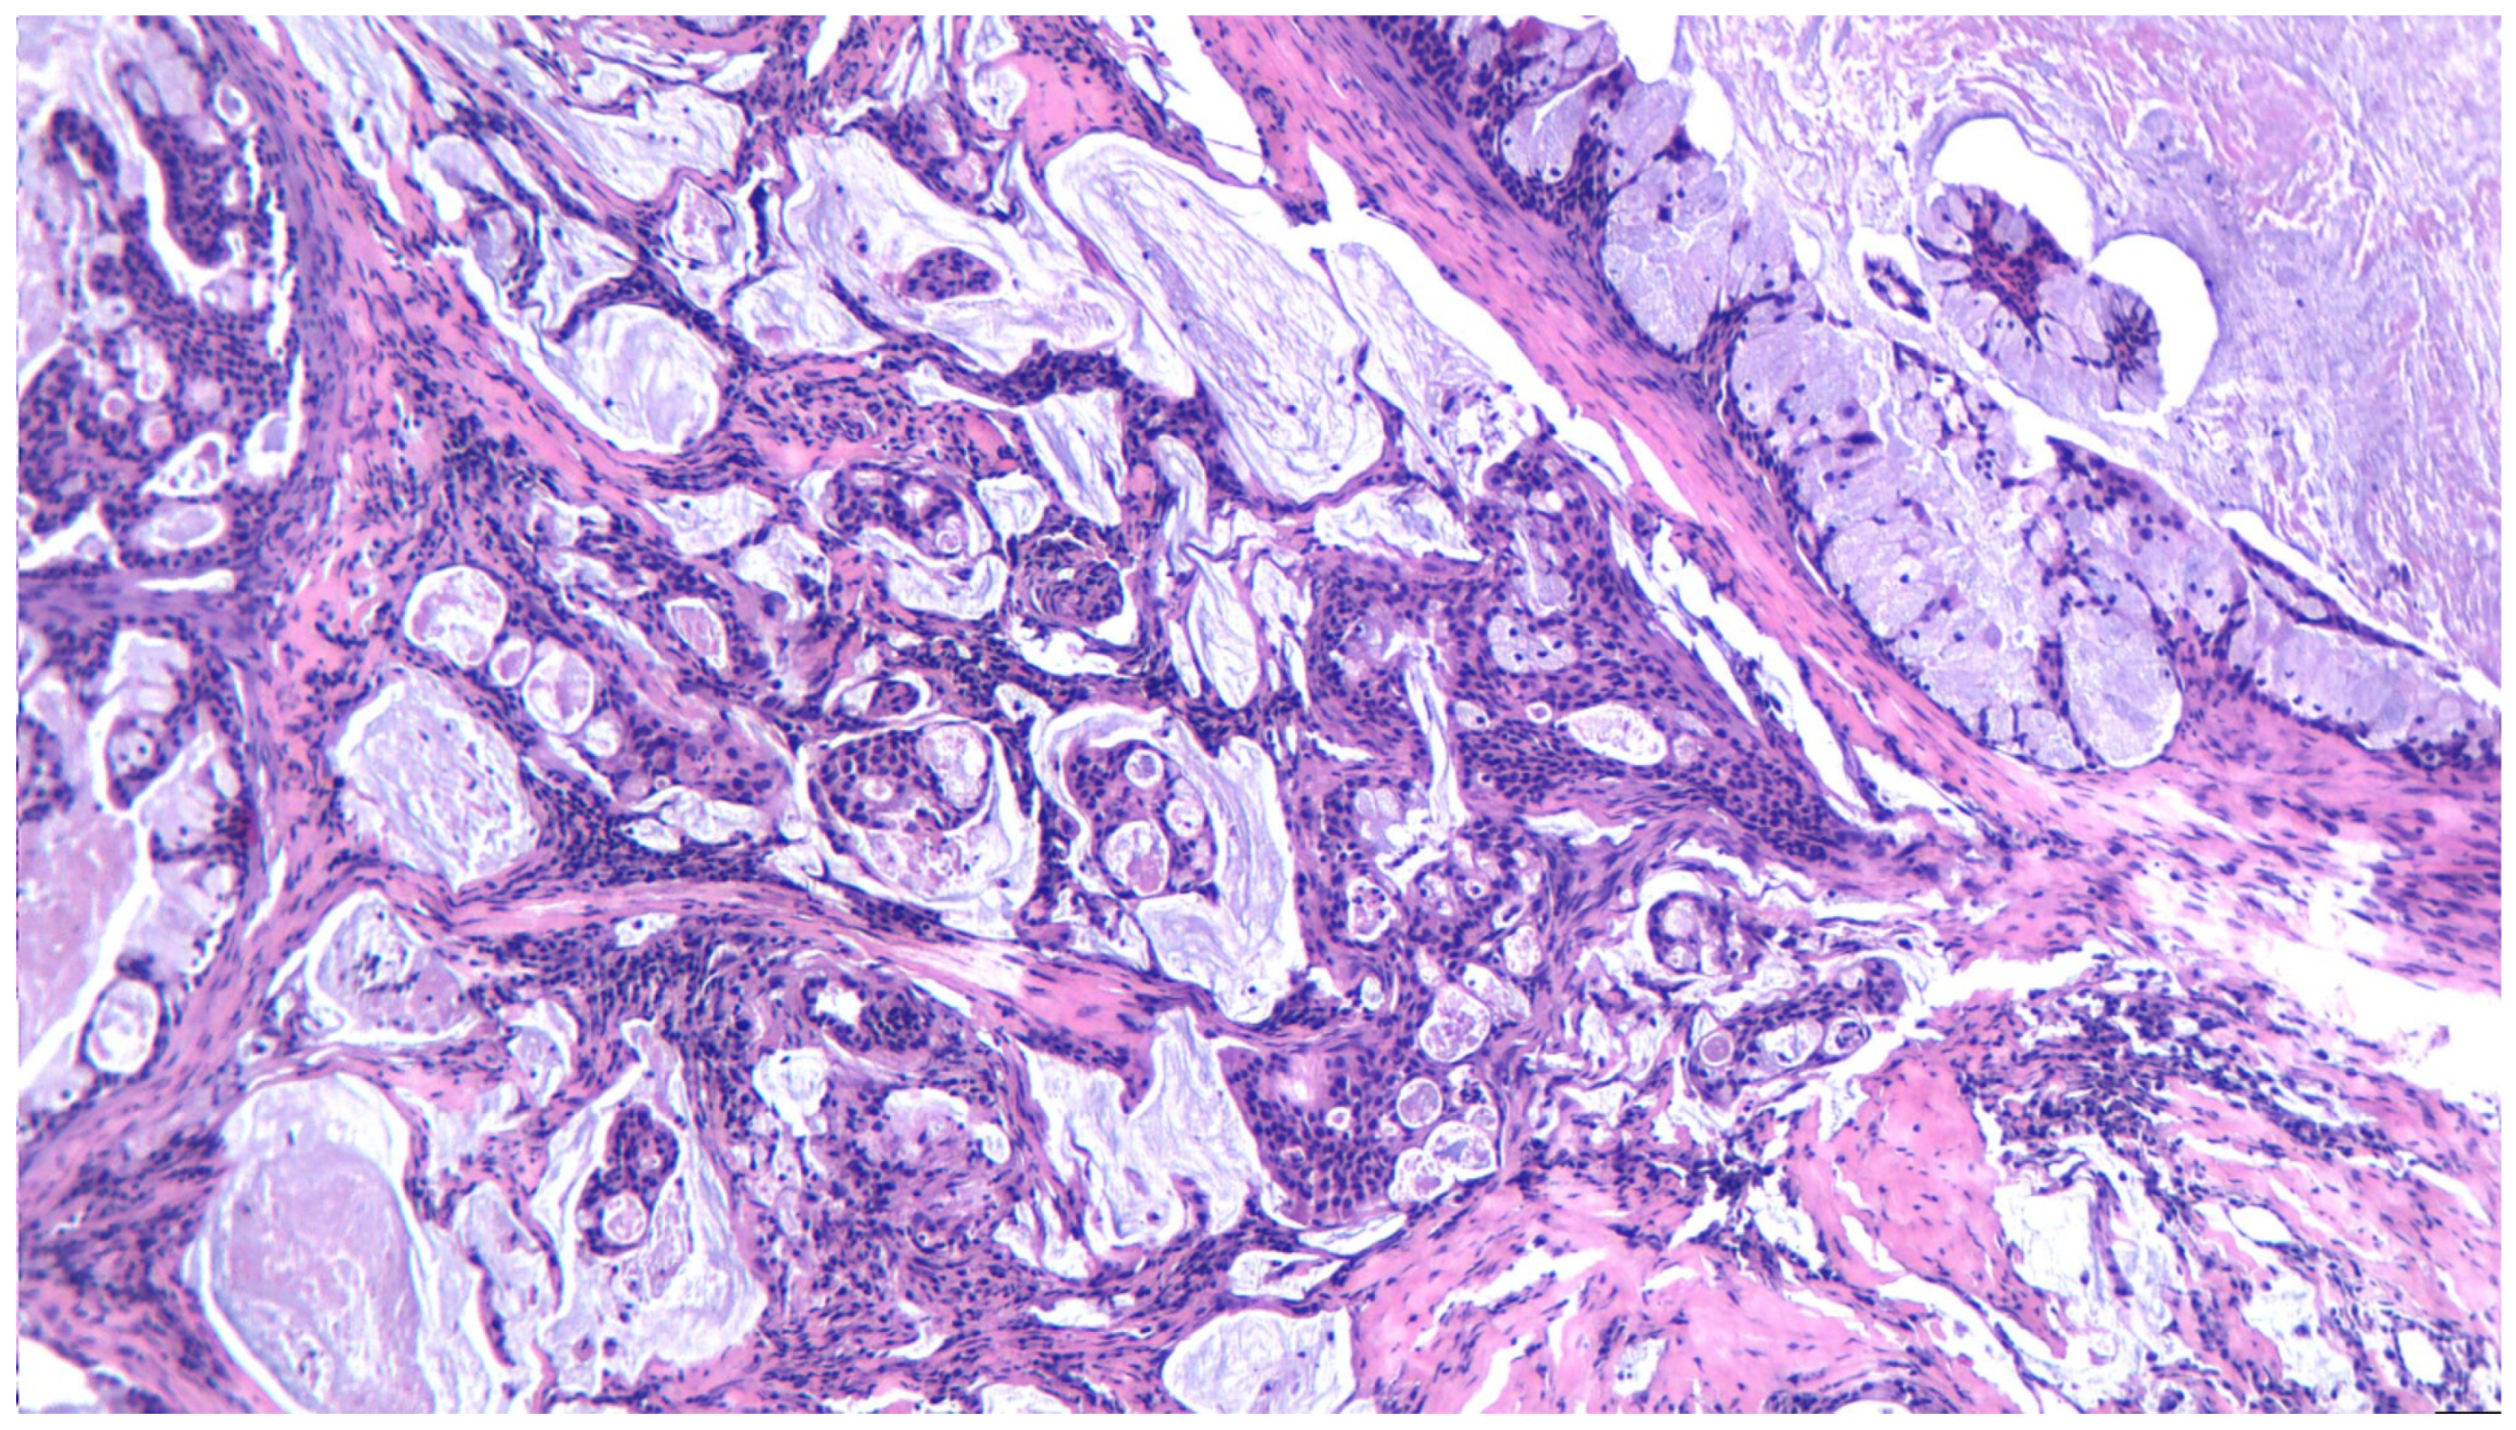

3.14. Mucoepidermoid Carcinoma